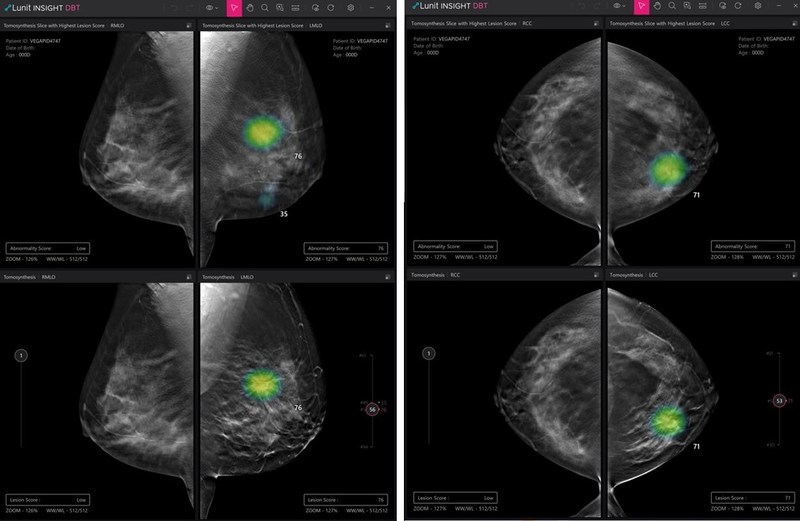

투자유치 소식에 이어 신제품 공개 소식도 전해졌다. ▲흉부 CT 데이터에 대한 AI 솔루션 '루닛 인사이트 체스트 CT(Lunit INSIGHT Chest CT)'와 ▲유방단층촬영(DBT)에 AI를 적용한 '루닛 인사이트 DBT(Lunit INSIGHT DBT)'가 그 주인공.

2개 신제품은 11월 28일부터 12월 2일까지 미국 시카고에서 열리는 북미영상의학회(RSNA)에서 첫 공개될 예정이다.

이번 RSNA에서 첫 공개될 루닛 인사이트 체스트 CT와 루닛 인사이트 DBT는 흉부 CT와 DBT 각각에 AI를 적용해 보다 빠르고 정확하게 판독해 의사 진단을 돕는 역할을 한다.

흉부 엑스레이와 유방조영술이 폐암과 유방암을 유발할 수 있는 질병을 1차적으로 발견하는 검사라면, CT와 DBT는 검출된 결절을 더 자세히 관찰해 암을 구별할 수 있는 보다 정교한 검사라 할 수 있다.

루닛 인사이트 체스트 CT는 흉부 CT 영상에서 검출된 결절의 위치, 유형, 부피, 크기 등을 3차원으로 자동 생성하는 솔루션이다. 루닛 인사이트 DBT는 AI를 활용해 병변이 의심되는 3차원 영상 이미지를 빠른 속도로 표시하는 솔루션이다. 이들 신제품은 기존 2차원 영상 진단에서 3차원으로 제품군이 확장됐다는 점에서 의미가 크다.

서범석 대표는 "이번 학회에서 내년 정식 출시를 앞둔 신제품 루닛 인사이트 체스트 CT와 루닛 인사이트 DBT를 처음 선보이게 돼 감회가 새롭다. 앞으로도 다양한 연구를 통해 학술적 신뢰도와 기술 정확도가 높은 제품을 지속 개발해 나갈 것"이라고 전했다.